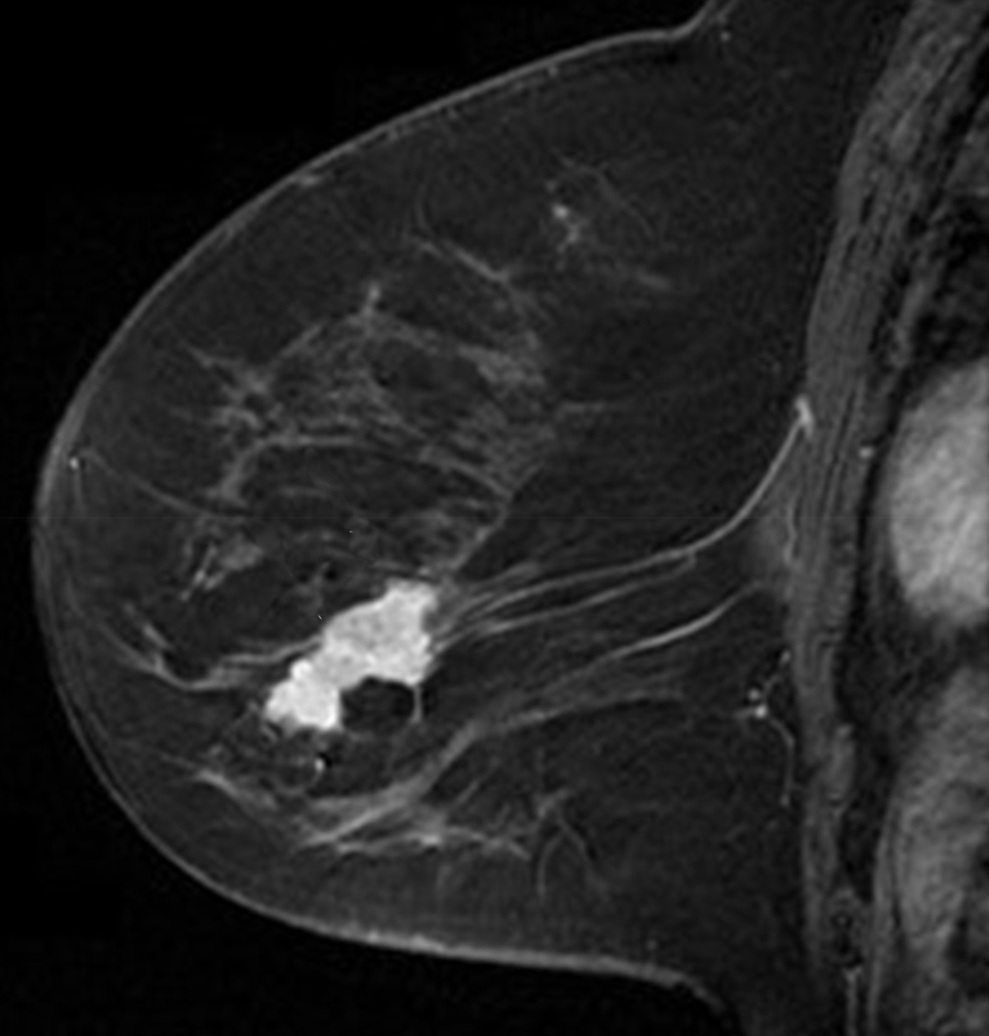

First we will use a Magnetic Resonance (MR) image of a female breast, taken from eby2008magnetic with permission from111www.slicer.org, to segment the tumor mass. On the top/right of Fig. 4, we see the first eigenfunction segmenting the tumor perfectly out of the breast image. Next, in the middle row of Fig. 4, we add to the image , of standard Gaussian noise, such that

where is i.i.d. Gaussian random variable with mean zero, variance equal to one and represents the noise level. Now, we compute the adaptive eigenspace of . Again, the first eigenfunction holds a nice segmentation of the tumor despite the additional noise. To demonstrate the quality of our approach, we consider the image but this time we destroy the boundaries of the tumor and change them by blurring (using an image manipulation program). The resulting image is shown on the bottom left of Fig. 4. On the bottom right of Fig. 4, we see the segmentation is accurate and captures the tumor and its blurred boundaries.

To reduce computational cost and get even more accurate results, we may create a Finite Element (FE) grid on the area of interest rather than on the image boundaries. For illustration, we consider the MR-images and shown on the top/left and bottom/left of Fig. 4, respectively. We automatically produce a mesh on the breast boundaries (see on the left of Fig. 5). The segmentation for and for is shown on the center and right of Fig. 5, respectively.